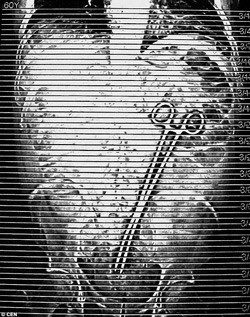

Chiếc ống tiêm bị bỏ quên trong cơ thể ông Zhang Huasau (Trung Quốc) khi được phẫu thuật trị viêm xoang.

Chiếc kẹp dài tới 38cm nằm trong bụng ông Pohl trong nhiều tuần sau khi thực hiện thủ tục thông một đoạn ruột bị tắc.